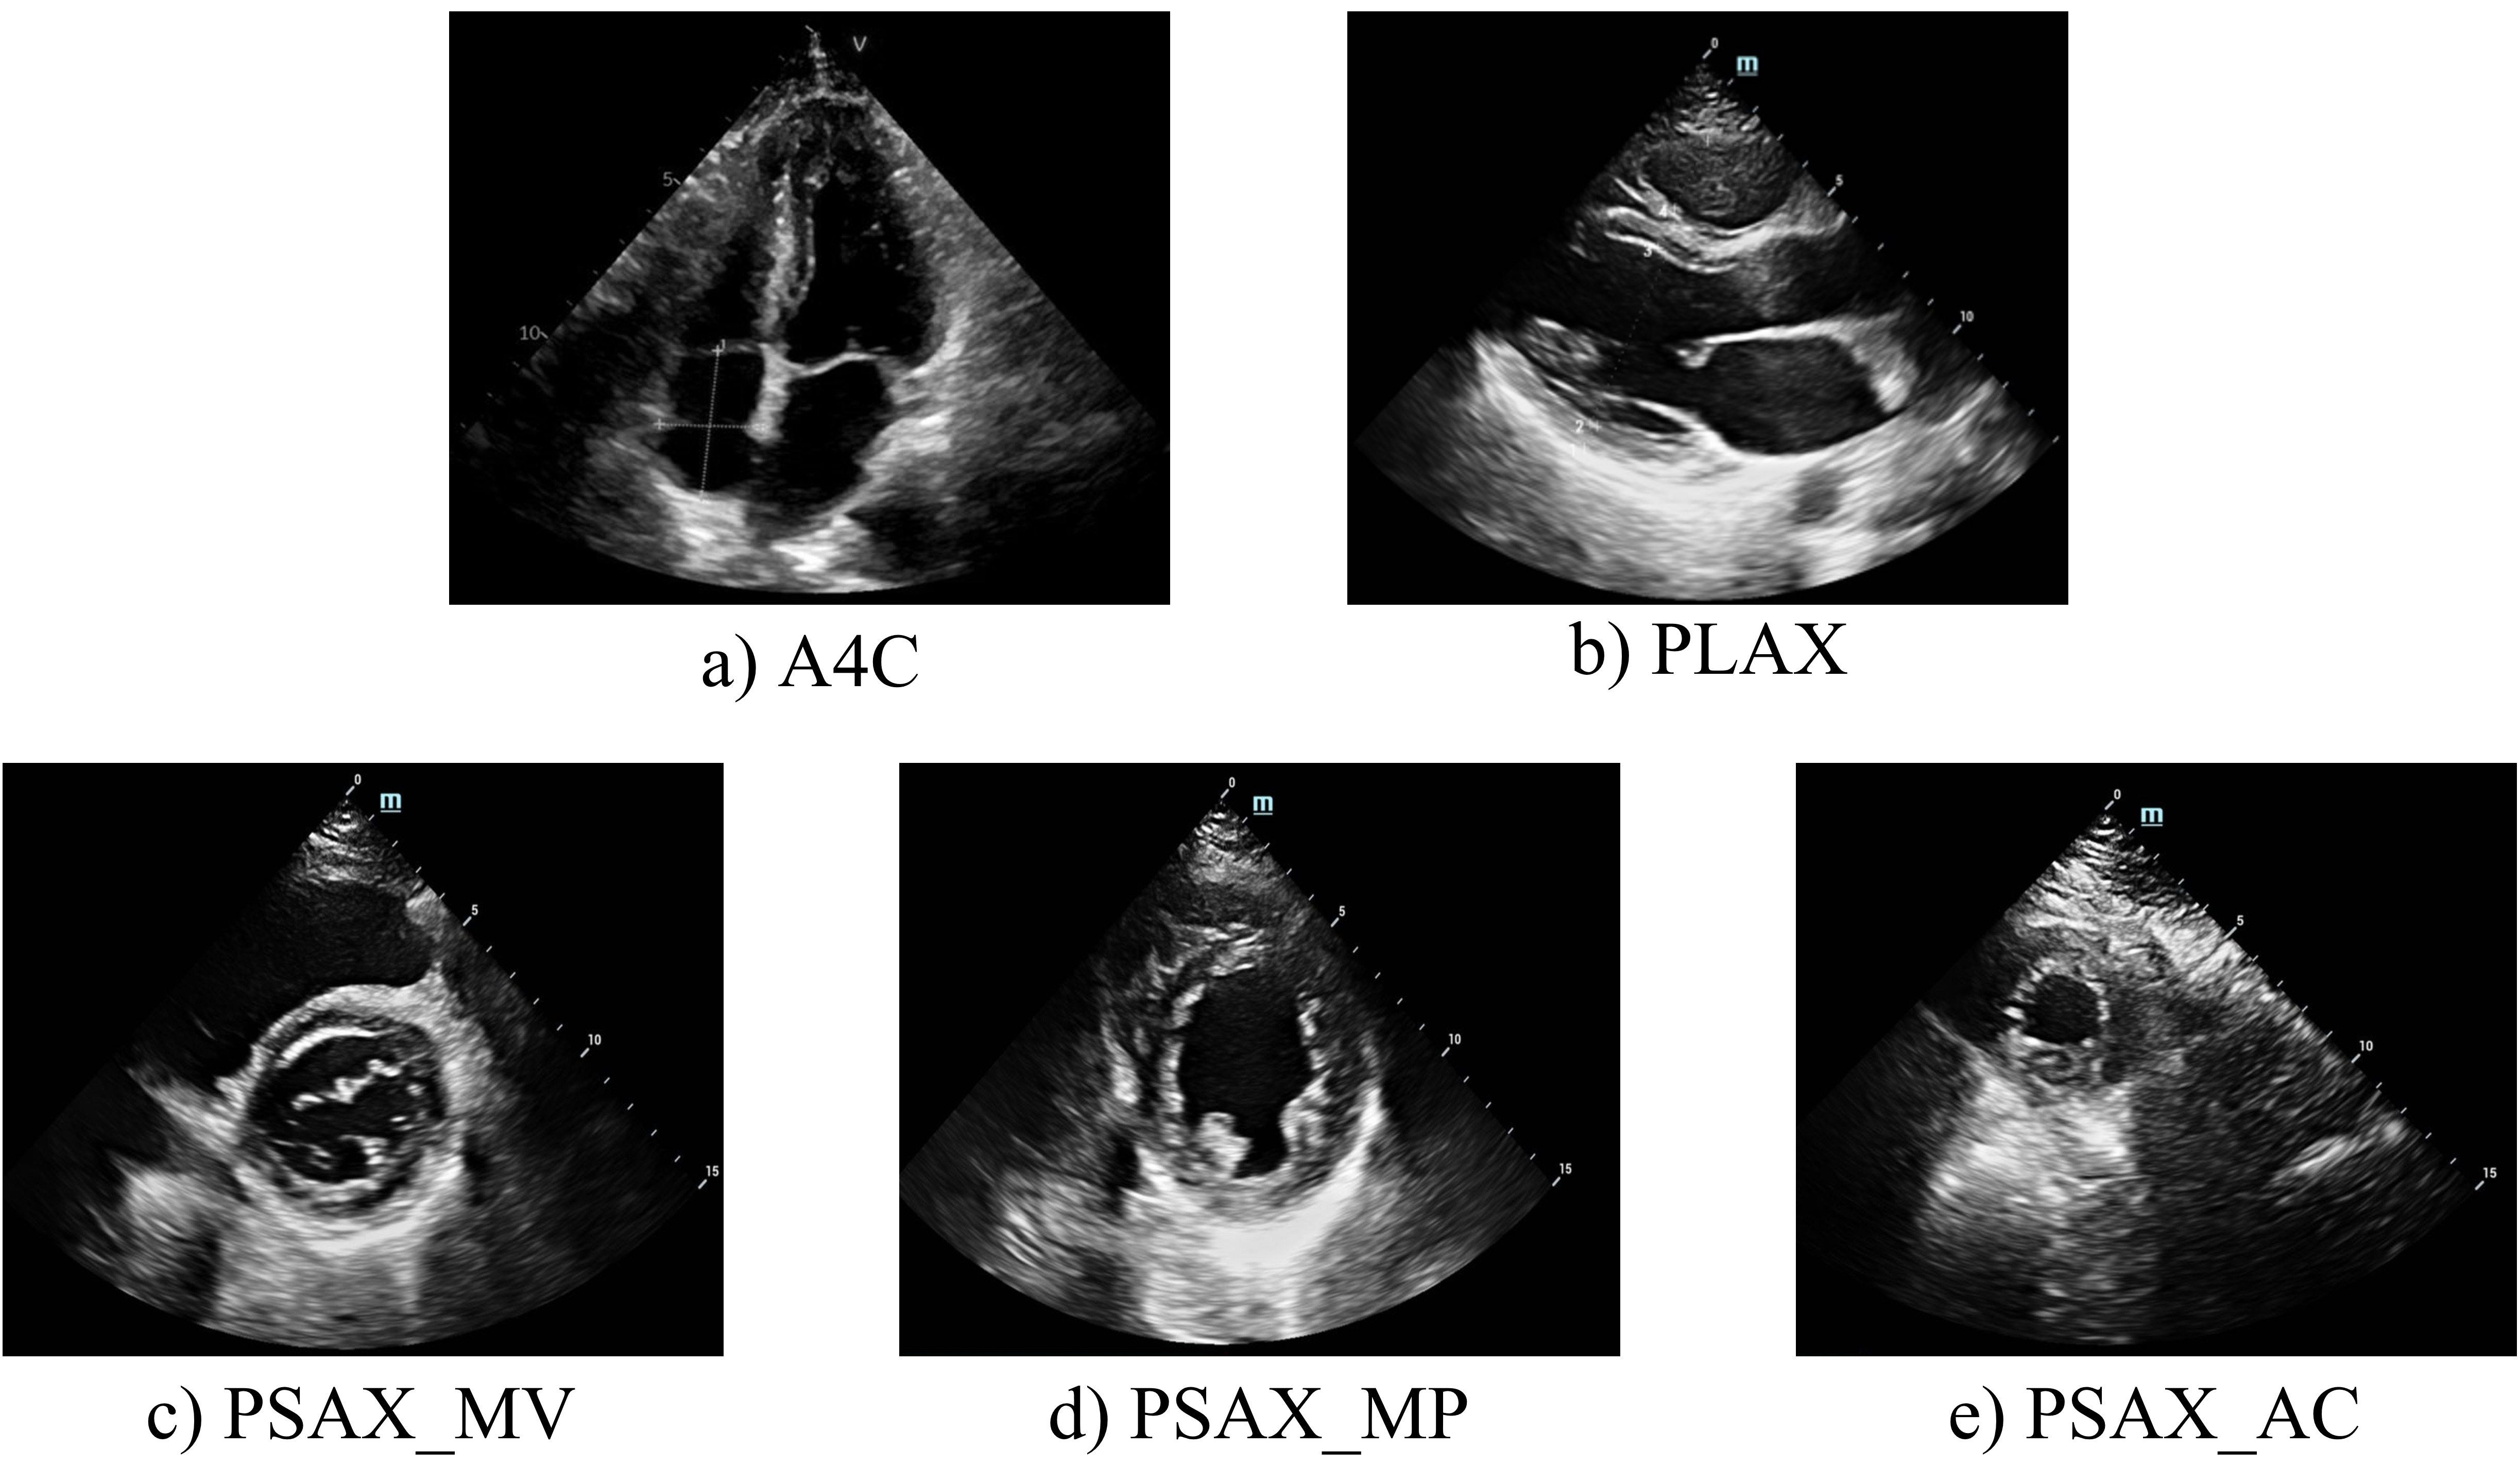

For each patient, five standard echocardiographic views were acquired (Fig. 2), with a set of normal cardiac function(Normal) data serving as the control group. These two-dimensional echocardiograms were captured by skilled echo doctors using various equipment and were stored in JPG format.

Within these five echocardiographic perspectives, the apical 4-chamber (A4C) view (as shown in Fig. 2 a) is particularly effective for evaluating the dimensions of each cardiac chamber and measuring the thickness of the left ventricular wall. The long-axis view of the parasternal left ventricle (PLAX) (Fig. 2 b) is instrumental in examining the left ventricle’s septum and posterior wall, among other structural aspects. This view plays a significant role in detecting various cardiomyopathy forms. The short axis series view of the heart (Fig. 2 c, d, e) provides a detailed perspective on the left ventricle’s wall thickness, echogenicity, motion amplitude, and segmental thickening rate. This comprehensive insight aids in the thorough understanding of the ventricular wall and enhances the identification of specific cardiomyopathy types. By functionally evaluating these views, we aim to distinguish and diagnose HCM and CA by integrating the characteristics observed across the selected five views.

Refer to caption

Figure 2: Cardiac imaging of five views. The second row is the short axis of arasternal left ventricular. a) A4C: apical 4-chamber, b) PLAX: Long axis of parasternal left ventricula, c) PSAX_MV: short axis at mitral valve, d) PSAX_MP: short axis at papillary muscle, e) PSAX_AC: short axis at apical